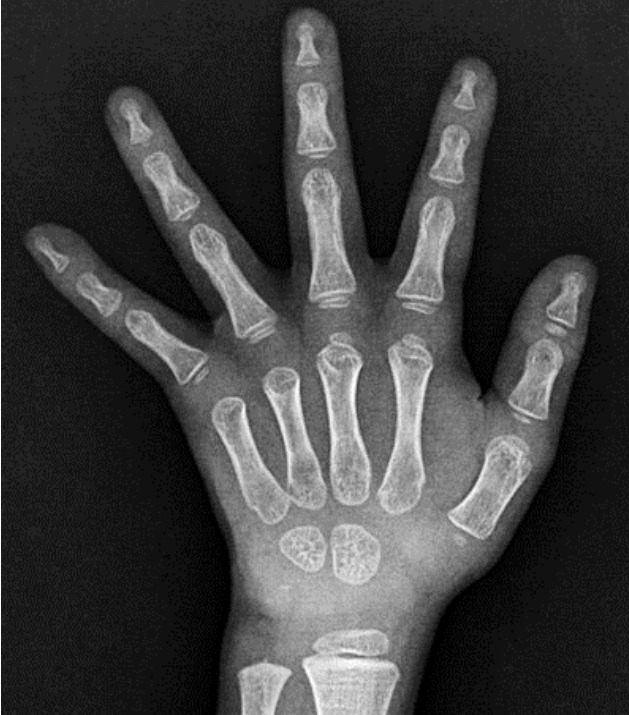

促甲状腺激素释放激素刺激试验显示TSH反应过度(基线TSH 7.02 μIU/ml; 30分钟88.55 μIU/ml; 60分钟73.4μIU/ml; 90分钟79.27μIU/ml; 120分钟64.41μIU/ml)。头颅磁共振造影未见垂体腺瘤证据;然而,发现了拉氏裂囊(图1)。甲状腺超声显示大小、轮廓、实质回声和血管性均正常,无结节。99m锝甲状腺扫描显示两侧甲状腺叶增大的摄取。

患者 12 个月大时的蝶鞍磁共振成像扫描。 除 Rathke 裂囊肿(箭头)外,矢状 T1 加权图像正常。